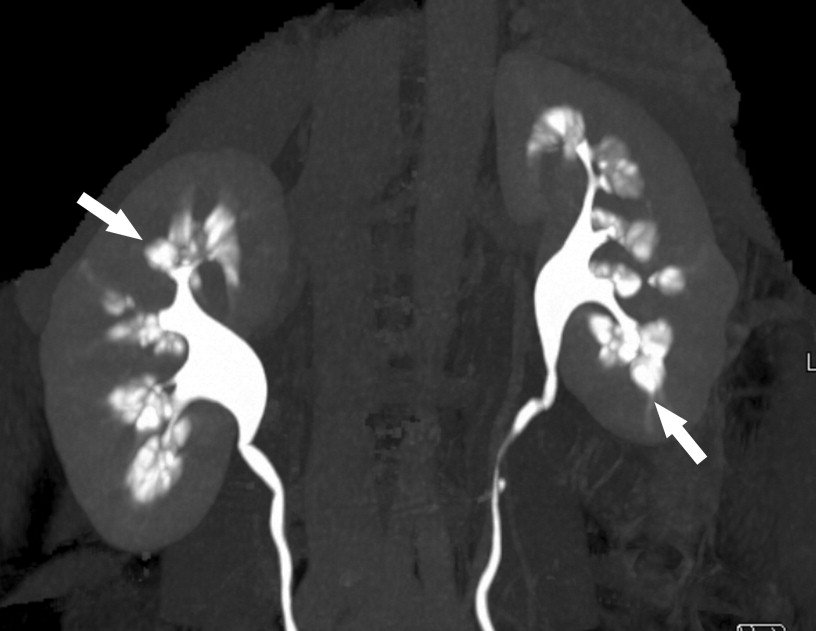

Medullary sponge kidney (MSK) is a developmental disorder of the kidneys characterized by dilated medullary and papillary collecting ducts, giving the kidney medulla a spongy appearance. On contrasted CT or IVP, typical findings include a papillary blush pattern that is often described as a bouquet of flowers or paintbrush appearance (see figure below). It typically affects both kidneys but can be unilateral. It is typically a sporadic disorder, but there are some familial clusters that suggest a genetic basis for the disease. MSK is associated with nephrocalcinosis, recurrent nephrolithiasis, renal tubular acidosis, and an increased risk for urinary tract infections. The most common manifestation of MSK is nephrolithiasis, with 70% of patients developing calcium stones. Stone formation is often recurrent and can be characterized by small “sand-like” stone formation. MSK usually presents in the 4th or 5th decade of life. Cysts can be found in the papillae of the affected kidney, and may communicate with the collecting system. The cause of MSK is unknown but there is growing evidence that it may be a ciliopathy, including some genetic studies. Treatment of MSK is supportive, and typically focused on treating hypercalciuria and hypocitraturia for prevention of calcium stones. Treatment with potassium citrate has been shown to decrease the stone event rate and improve bone density in patients with MSK.

Figure Contrast-enhanced maximum intensity projection 3-dimensional image from multidetector-row computed tomographic urogram shows characteristic papillary blush (arrows) associated with scattered calculi within the dilated collecting tubules. The computed tomographic demonstration is equivalent to the well-documented intravenous pyelography findings.